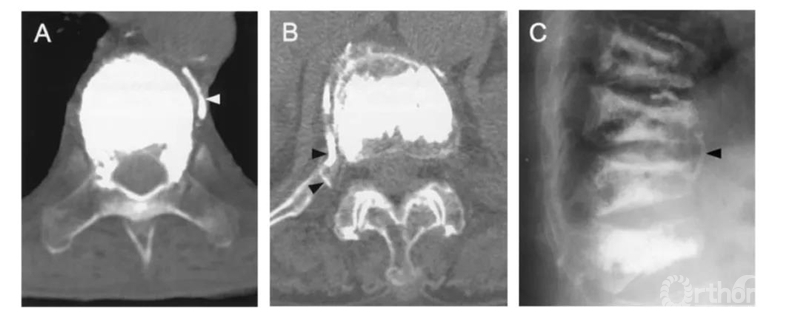

比如这例,侧位X片看骨水泥在椎弓根里,可CT一扫发现已经渗漏进入椎管。

侧位X片看骨水泥在椎体里,CT显示渗漏进入椎管。

侧位X片看骨水泥在椎间孔周缘,CT显示渗漏进入椎管,累及椎间孔。